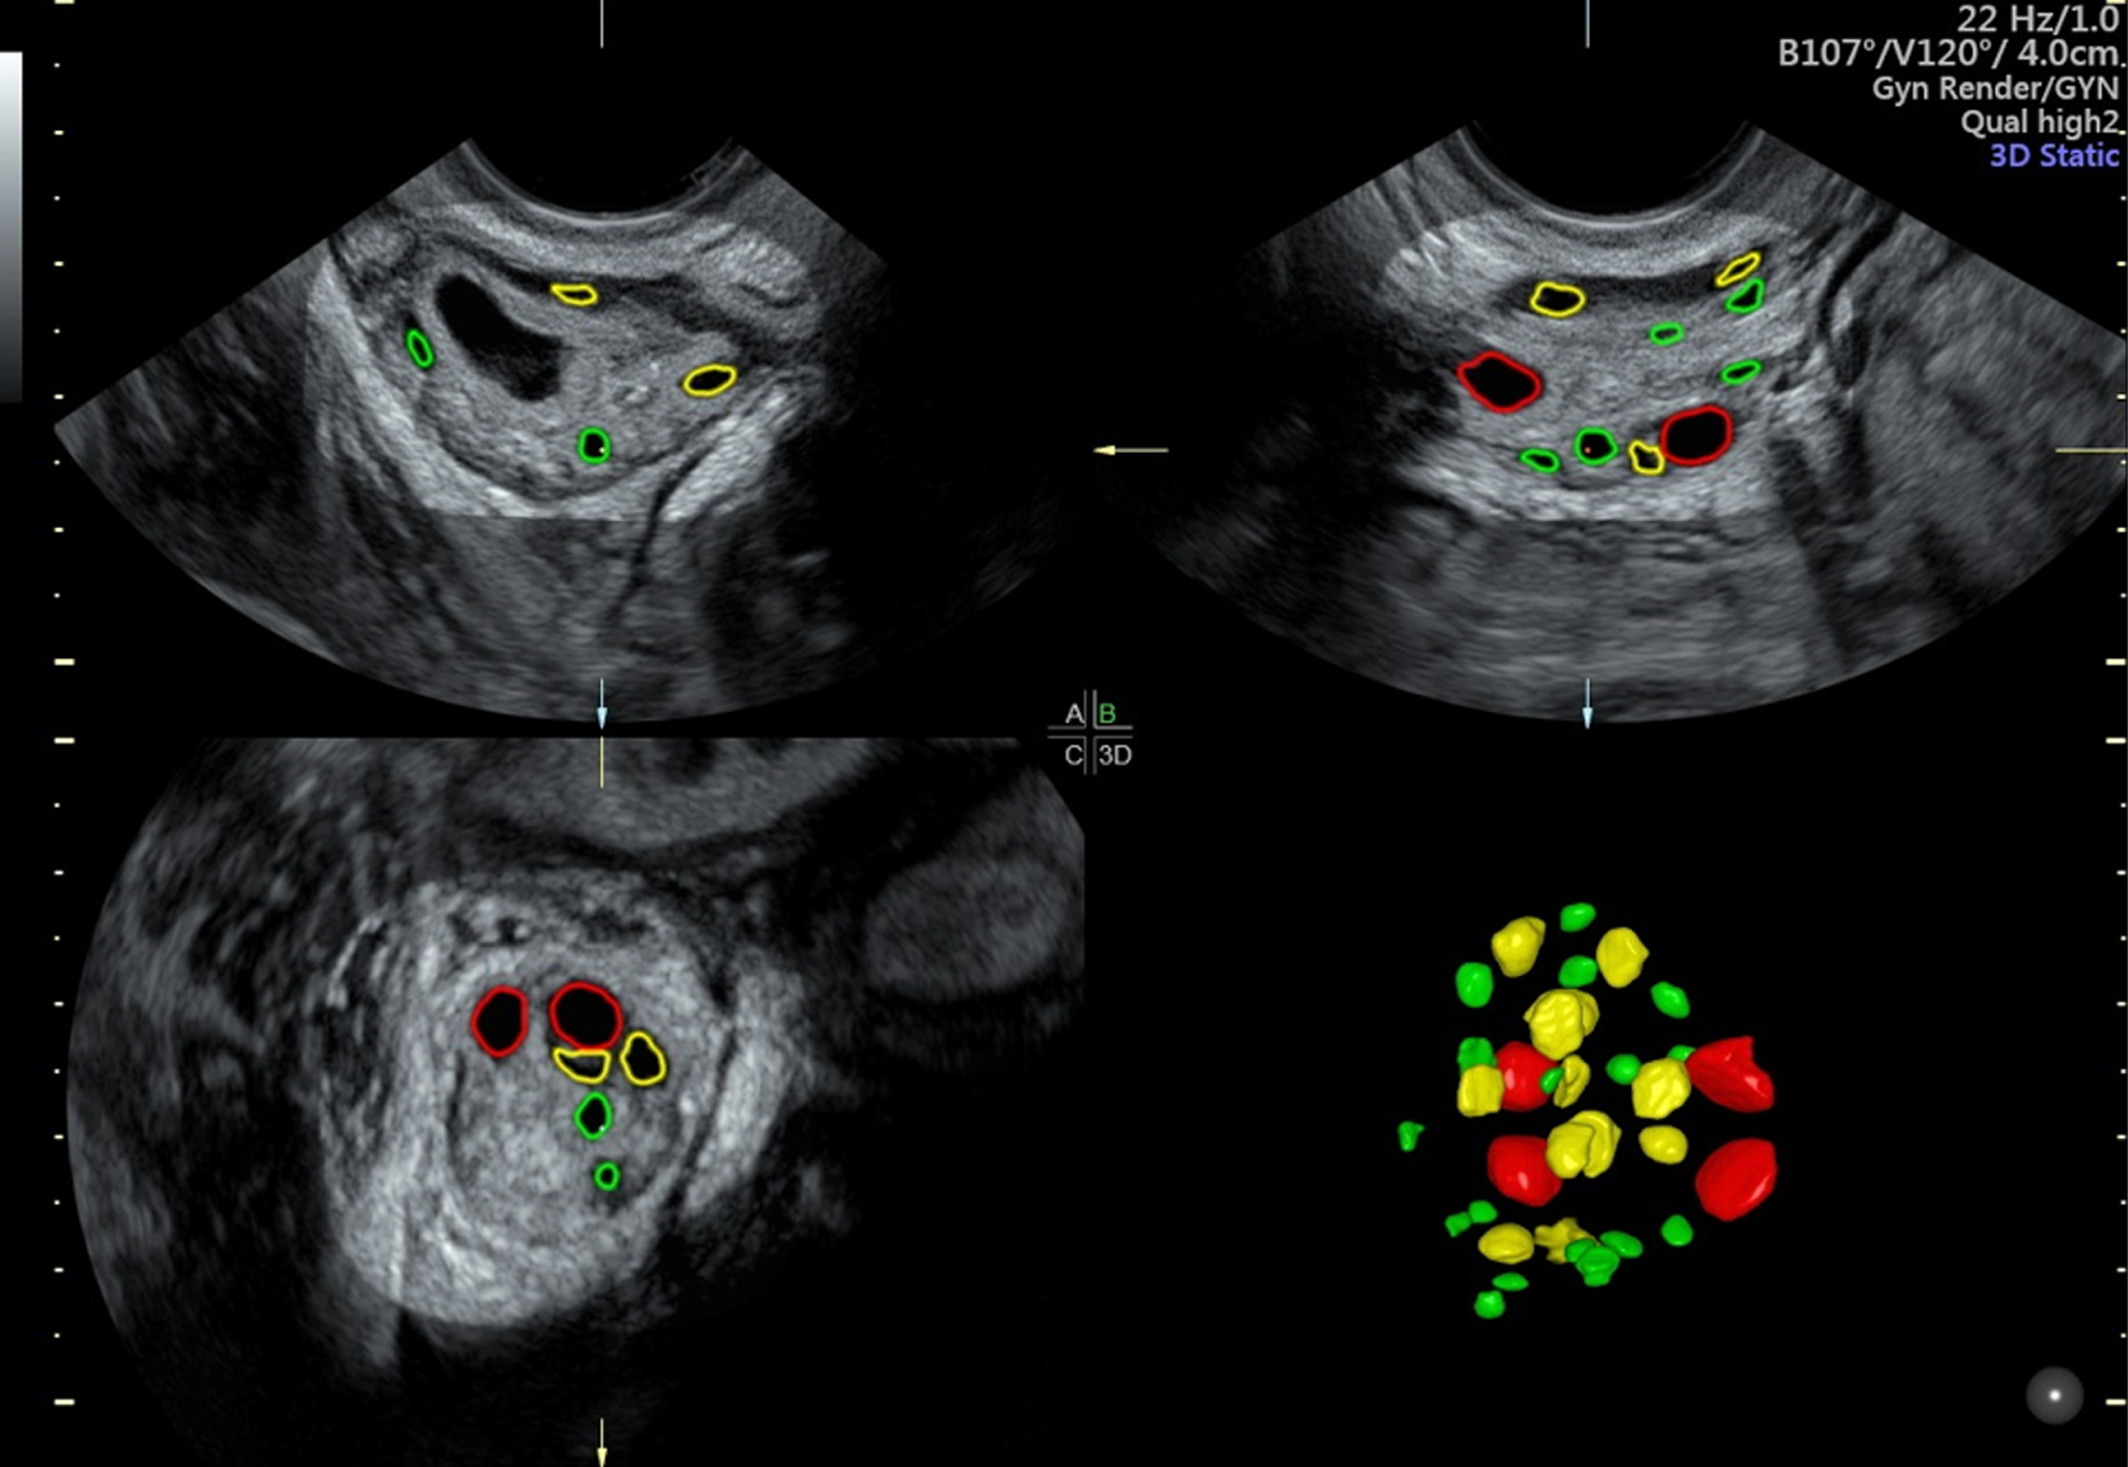

USG, 3D-4D, TVS Automated Follicle Count

Latest imaging technology for accurate diagnosis and fertility monitoring including 3D/4D ultrasound and follicle count.